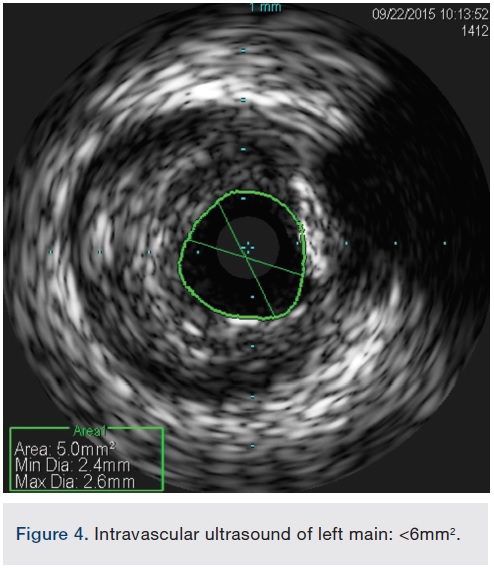

Following successful completion of the peripheral phase, it was felt that a 4-week period was necessary for the iliac stent to heal somewhat (especially since we planned to place a 14 French Cook sheath through it). We then moved on to the coronary phase of this procedure. Bilateral groins and the right wrist were prepared and draped in the usual sterile fashion. Using micropuncture technique with fluoroscopic verification of needle entry into the left CFA at the upper quadrant of the femoral head, a 6 French sheath was placed in the left CFA. The existing left femoral arterial sheath was removed, and the arteriotomy was pre-closed with a single Perclose device (Abbott Vascular). The arteriotomy was then serially dilated with 10, 12 and 14 French dilators, and a 14 French, 30 cm Cook sheath was placed successfully in the left common femoral artery. Following therapeutic anticoagulation with intravenous heparin, a regular J-wire and a 6 French pigtail catheter were used to cross the aortic valve, and the catheter was used to exchange the J wire for the 0.018-inch Platinum Plus wire (Boston Scientific). The Impella CP (3.5) percutaneous left ventricular assist device (LVAD) (Abiomed) was inserted into the left ventricle over the Platinum Plus wire (Figure 8). The Impella was then activated and good flows were verified. Right radial artery access was obtained and a PB 3.0 7.5 French sheathless guide system (Asahi Intecc) was used to engage the left main coronary artery. The LAD was wired uneventfully using a Runthrough wire (Terumo) via a 1.25 x 6 mm over-the-wire (OTW) Sprinter balloon (Medtronic). This was then exchanged for a Viper wire (CSI). Orbital atherectomy of the proximal LAD lesion was performed with excellent results (80,000 rpm x 4 passes, 120,000 rpm x 2 passes) (Figure 9). The LAD wire was then exchanged for a Runthrough wire and the left circumflex (LCX) was wired with a BMW wire. Following plaque modification with orbital atherectomy, predilation of LAD was performed with 3.0 x 20 mm Chocolate Balloon (QT Vascular Ltd) (15 atmospheres x 60 seconds and 15 atmospheres x 30 seconds) (Figure 10) with an excellent result and no dissection (Figure 11). A 3.5 x 38 mm Promus stent (Boston Scientific) (14 atmospheres x 30 seconds) was placed from the left main into the proximal LAD lesion ensuring adequate coverage. The jailed LCX wire was recovered and re-placed in the LCX through the struts of the newly placed LM-LAD stent (Figure 12). Predilation of the LCX ostium was performed with a 2.5 x 8 mm Glider balloon (QT Vascular Ltd) (14 atmospheres x 25 seconds). The mid LAD was stented (ensuring overlap with proximal stent) with 3.0 x 16 mm Promus stent (16 atmospheres x 25 seconds). A final kissing balloon inflation of the LAD/LCX with an NC Sprinter 2.5 x15 mm balloon (Medtronic) into the LCX and a NC Sprinter 3.5 x12 mm balloon into the LAD was performed, with up to 16 atmospheres x 20 seconds on both (Figure 13). Final IVUS of the LM and LAD stent revealed excellent results and the LCX ostium looked excellent as well (Figures 14-16).